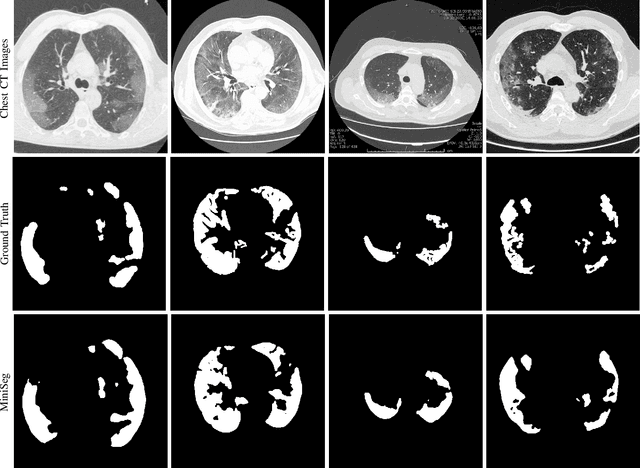

The rapid spread of the new pandemic, coronavirus disease 2019 (COVID-19), has seriously threatened global health. The gold standard for COVID-19 diagnosis is the tried-and-true polymerase chain reaction (PCR), but PCR is a laborious, time-consuming and complicated manual process that is in short supply. Deep learning based computer-aided screening, e.g., infection segmentation, is thus viewed as an alternative due to its great successes in medical imaging. However, the publicly available COVID-19 training data are limited, which would easily cause overfitting of traditional deep learning methods that are usually data-hungry with millions of parameters. On the other hand, fast training/testing and low computational cost are also important for quick deployment and development of computer-aided COVID-19 screening systems, but traditional deep learning methods, especially for image segmentation, are usually computationally intensive. To address the above problems, we propose MiniSeg, a lightweight deep learning model for efficient COVID-19 segmentation. Compared with traditional segmentation methods, MiniSeg has several significant strengths: i) it only has 472K parameters and is thus not easy to overfit; ii) it has high computational efficiency and is thus convenient for practical deployment; iii) it can be fast retrained by other users using their private COVID-19 data for further improving performance. In addition, we build a comprehensive COVID-19 segmentation benchmark for comparing MiniSeg with traditional methods. Code and models will be released to promote the research and practical deployment for computer-aided COVID-19 screening.